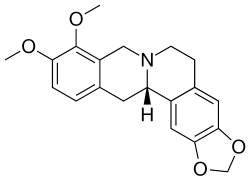

Many of the species in Corydalis contain alkaloids such as canadine and corydaline, which blocks calcium. The majority of these belong to the isoquinoline alkaloid group.[2] All parts of the plant are alkaloidal but the highest concentrations are present in the hollow root tuber.

Corydalis cava and some other tuberous species contain the alkaloid bulbocapnine, which is occasionally used in medicine but for which scientific evidence is lacking in regard to correct dosage and side effects.[3]